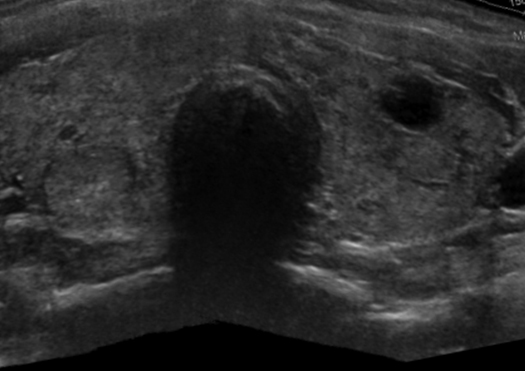

Ultrasonido o Ecografía

Es una técnica que utiliza ondas sonoras de alta frecuencia, que no son percibidas por el oído humano, con frecuencias entre 2 a 20 megahertz, para crear imágenes de los órganos del cuerpo. Tiene la función de adquirir imágenes en 2D, 3D y 4D.